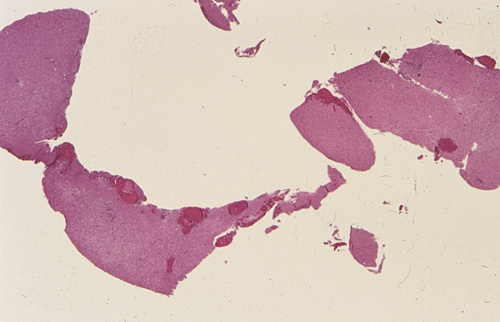

Streotactic biopsy yielded several cores of tissue. On scanning magnification, there are multiple small lymphocytic collections (Ž in Panel C) in the white matter. On higher magnification, these areas contain mostly lymphocytes without atypia. These collections appear to be angiocentric and are often admixed with some foamy macrophages (Panel  D and E). On LFB/PAS stain, multiple small, irregular areas of angiocentric pale staining are present (Panel F and G). On high magnification, these areas are featured by infiltration by foamy macrophages and lymphocytes and myelin loss (Panel  H). On Bielschowsky stain, the axons in these pale areas are largely preserved. Immunohistochemistry on GFAP demonstrates multiple stellate reactive astrocytes (Panel J). The macrophages and lymphocytes are also well demonstrated by immunohistochemistry for CD68 and LCA respectively (Panel  K and L).

The histopathology of inflammatory demyelinating pseudotumors is very similar to that of acute disseminated perivsnous encephalomyelitis or the classic type of ADEM. In essence, there is perivenous chronic inflammatory cell infiltration accompanied by infiltrating, foamy macrophages with an angiocentric distribution. Loss of myelin and relative preservation of axon fibers must be demonstrated before a diagnosis of demyelinating process is made. The loss of myelin can be well demonstrated by special stains for myelin with the Luxol fast blue based stains as one of the most commonly used stains. Relative preservation of axons can be sell demonstrated by silver stains such as Bodian stain, Bielschowsky stain, and also immunohistochemistry for moderate and high molecular weight neurofilament proteins. The pathologic highlights on separating inflammatory demyelinating lesions from mimicking lesions have been well described by Zagzag et al. 8. Other inflammatory lesions, particularly viral infectons, must also be ruled out. Keen observations particularly for nuclear inclusion bodies, immunohistochemistry for specific viral agents, and laboratory studies of the cerebral spinal fluid (CSF) and blood are often helpful. Identification of oligoclonal bands on electrophoresis of CSF is a strong suggesting of a demyelinating process.